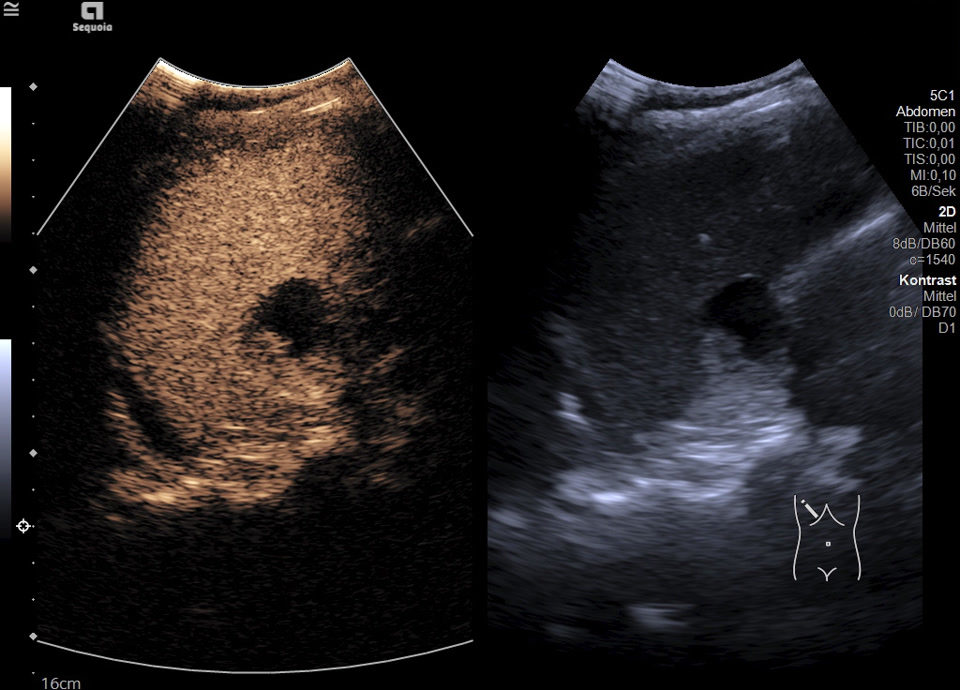

Es zeigt sich subkapsulär in Segment VI der Leber eine zystische Raumforderung mit durchgehendem Kapselreflex und hyperechogenem solidem Anteil. Der Befund ist nicht vereinbar mit einer blanden Zyste, sondern suspekt auf eine zystisch-solide Metastase. In der ergänzenden CEUS nehmen die soliden Anteile in der arteriellen Phase Kontrastmittel auf und zeigen in den portalvenösen sowie späten Phasen eine persistierende KM-Anreicherung ohne Washout. Zusätzlich finden sich eine noduläre Peritonealverdickung im Oberbauch sowie ein zystischer Ovarialtumor mit soliden Anteilen im rechten Unterbauch. In Zusammenschau der Befunde besteht der dringende Verdacht auf ein hepatisch und peritoneal metastasierendes Ovarialkarzinom.